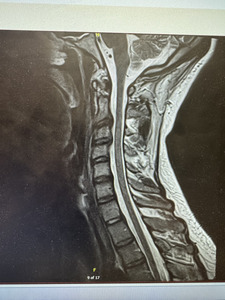

Diagnostic Assessment: Radiographic imaging was instrumental in identifying structural contributors to the patient’s ongoing symptoms. Thoracic X-rays revealed dextroscoliosis at the T5/T6 level, with visible surgical clips at the right T1 rib and a residual segment of the first rib remaining on the left side, suggesting an incomplete prior resection (see Figure 1). Further evaluation with cervical MRI demonstrated mild degenerative changes, including canal stenosis at C3-C4 and mild right neural foraminal stenosis at the same level. Additionally, a disc osteophyte complex was identified at C2-C3, causing effacement of the ventral thecal sac (see Figure 2). Subsequent surgical intervention confirmed the presence of the residual first rib segment on the left, which was successfully excised during the revision procedure (see Figure 3).